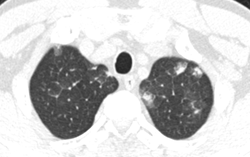

Không tẩy giun nhiều năm, người đàn ông bị sốt, tức ngực do mắc hội chứng ít ai biết

Phòng & chữa bệnh 12:40 26/05/2023Người đàn ông nhập viện trong tình trạng sốt thất thường, ho khạc đờm, tức ngực 1 tuần không đỡ.